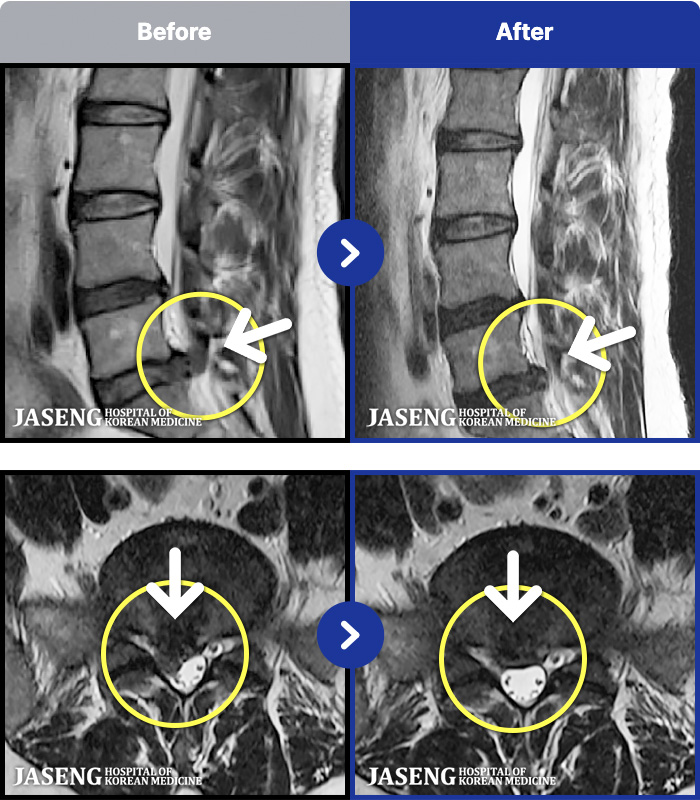

MRI ũ ʸ Ȯϼ.

MRI ġ

㸮 ٸ

ǿ

â

ȯ

㸮ũ

[â] 18.09.11~19.09.18

ȯںп Ǹ ǿ ԿǾ, ο ġ ۿ Ƿ ġḦ Ͻñ ٶϴ.

[Կñ:18.09.11~19.09.18]

[â_㸮ũ] 㸮 ٸ